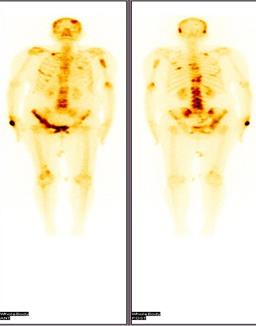

It is easy to use, widely available and less expensive. Moreover it does not use any ionizing radiation, gives a clearer picture of soft tissue that cannot be seen in X-rays, causes no health problems and can be repeated as much as can if indicated for any health problems. It provides real-time-imaging so Is perfectly good for minimally invasive procedures such as needle biopsy and fluid aspiration. The disadvantages if the transrectal USG is that the patients with their bowel removed during or prior surgery are not good candidates for USG of the prostate as it always require a placing a probe into the rectum.

When prostate cancer is suspected, the diagnostic test of choice is a systematic needle biopsy with US guidance. Before biopsy, the patient is prepped with an enema and antibiotics (quinolone analogs). With the patient in the decubitus position, the transrectal US probe is placed in the rectum, the prostate and seminal vesicles are visualized, and the images are recorded in transverse and sagittal planes. And moreover the biopsy can be taken simultaneously under the USG guidance. A single biopsy session has a sensitivity of 70%–80% for the detection of cancer. To minimize the need for repeat biopsy sessions, many physicians obtain more cores the first time. Separate samples of the anterior prostate (or transition zone) are usually not obtained unless previous biopsy sessions have failed to find a suspected cancer (eg, in a patient with a high PSA level, abnormal findings at digital rectal examination [DRE], and multiple negative peripheral zone biopsy specimens), or imaging with transrectal US or MR suggests an anterior cancer [[103]].

Diagnostically, transrectal US is used to measure the volume of the prostate gland, an important factor in computing “PSA density” (serum PSA level in nanograms per millilitre divided by the volume of the prostate in cubic centimetres). Moreover, the volume as measured with transrectal US can be used in staging and in predictive nomograms. Cancer, depending on its size, grade, and location, usually appears hypoechoic relative to the normal peripheral zone of the prostate (only approximately 1% are hyperechoic). As a diagnostic test for cancer, transrectal US without biopsy is as accurate as DRE and complements the physical examination. Some palpable cancers are not visible at US, and some visible cancers are not palpable. With the shift toward smaller, early-stage cancers, many cancers detected at biopsy are not visible at US (low sensitivity) and many hypoechoic areas do not prove to be malignant at biopsy (low specificity); therefore, transrectal US alone, without the addition of biopsy, has limited value in the detection of cancer [[104]].

Transrectal ultrasound has been used for the staging of primary cancer but is generally considered insufficient. The criterion for identifying extracapsular extension on transrectal US scans are bulging or irregularity of the capsule adjacent to a hypoechoic lesion. The length of the contact of a visible lesion with the capsule is associated with the probability of extracapsular extension. Seminal vesicle invasion (SVI) is heralded by a visible extension of a hypoechoic lesion at the base of the prostate into a seminal vesicle or by echogenic cancer within the normally fluid-filled seminal vesicle. Asymmetry of the seminal vesicles or solid hypoechoic masses within the seminal vesicles are indirect indicators of disease extension. When extraprostatic extension into the seminal vesicles is suspected, additional transrectal US-guided biopsies of the seminal vesicles can be performed.